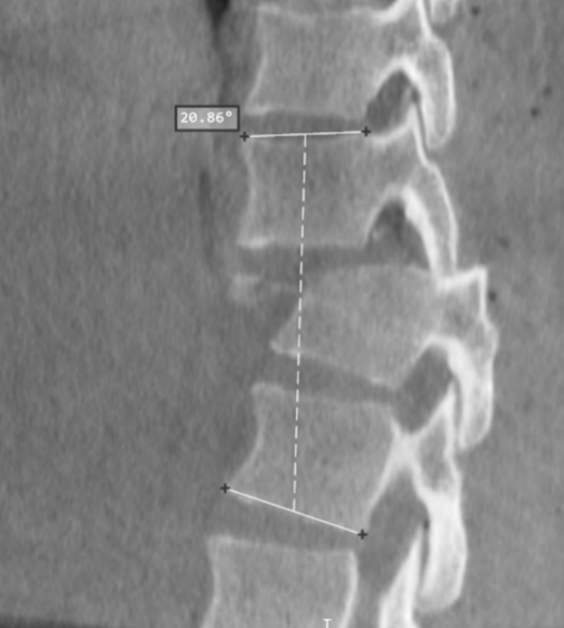

Scoliosis means your spine curves sideways. It can happen in children or adults and might require treatment if it is severe or causes pain.